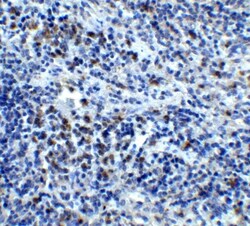

CXCR4 Polyclonal specifically detects CXCR4 in Human, Mouse, Rat samples. It is validated for Western Blot, ELISA, Immunohistochemistry, Immunocytochemistry/Immunofluorescence, Immunohistochemistry-Paraffin, Knockdown Validated.

| Western Blot 1-2 μg/mL, ELISA 1:100-1:2000, Immunohistochemistry 5 μg/mL, Immunocytochemistry/Immunofluorescence 4 μg/mL, Immunohistochemistry-Paraffin 5 μg/mL, Knockdown Validated | |